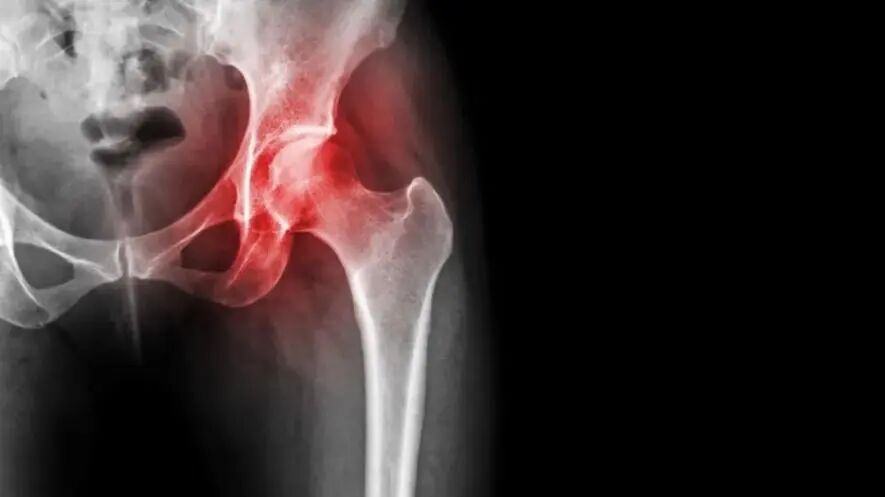

1期:X线片正常,但MRI或骨扫描呈阳性;

2期:X线片异常(股骨头内骨硬化,局灶性骨质疏松,或囊性变等细微征象),但无任何证据显示软骨下骨骨折,坏死区骨折,或股骨头变扁;

3期:X线片或CT可见软骨下骨或坏死区骨折。该期进一步分为两个亚期:3A期(股骨头塌陷≤2mm)和3B期(股骨头塌陷>2mm);

4期:X线片有骨关节炎证据,伴随关节间隙变窄,髋臼侧改变,伴/不伴关节破坏。